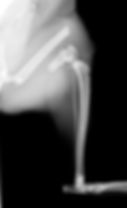

診断は主にレントゲン検査で行います。

どの位置で折れているか

骨のズレはどれくらいか

関節に影響していないか

その他の骨折などはないか

を確認し、治療方針を決めます。

プレートやピンなどの金属を使って骨を固定

正しい位置に戻し、しっかり癒合させる

という処置を行います。